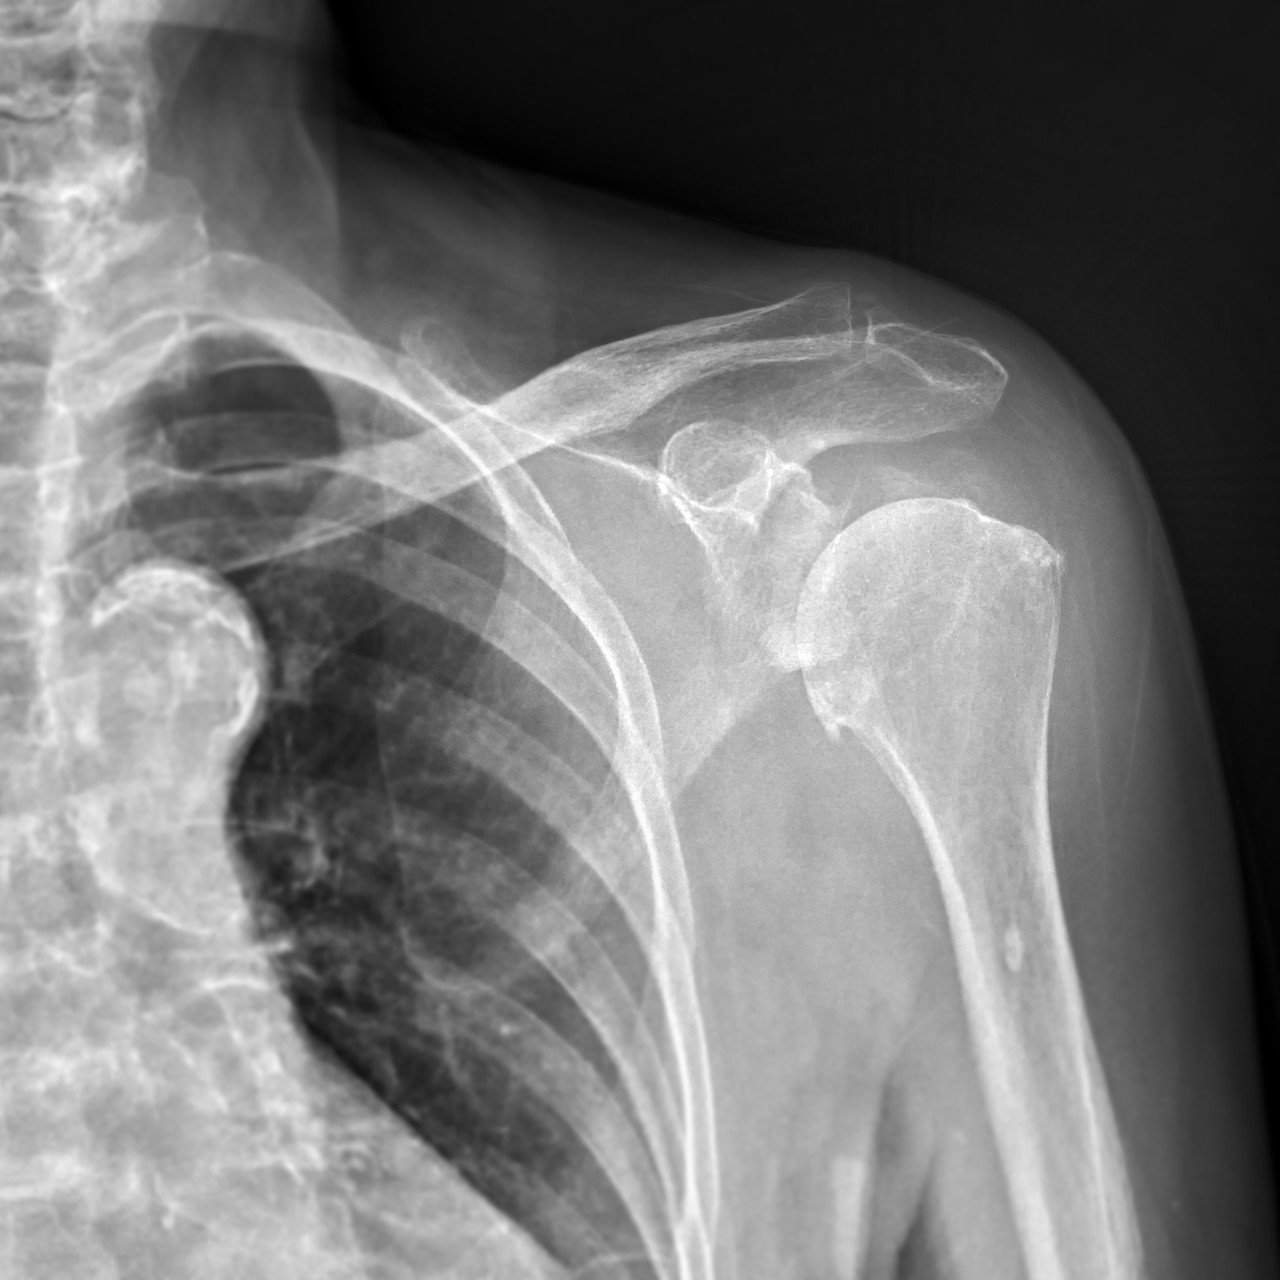

정밀진단

원장님과 상담 후 X-ray, 초음파 등 정밀 장비를 이용하여 정확하게 분석한 후 해당 결과를 토대로 재상담을 진행